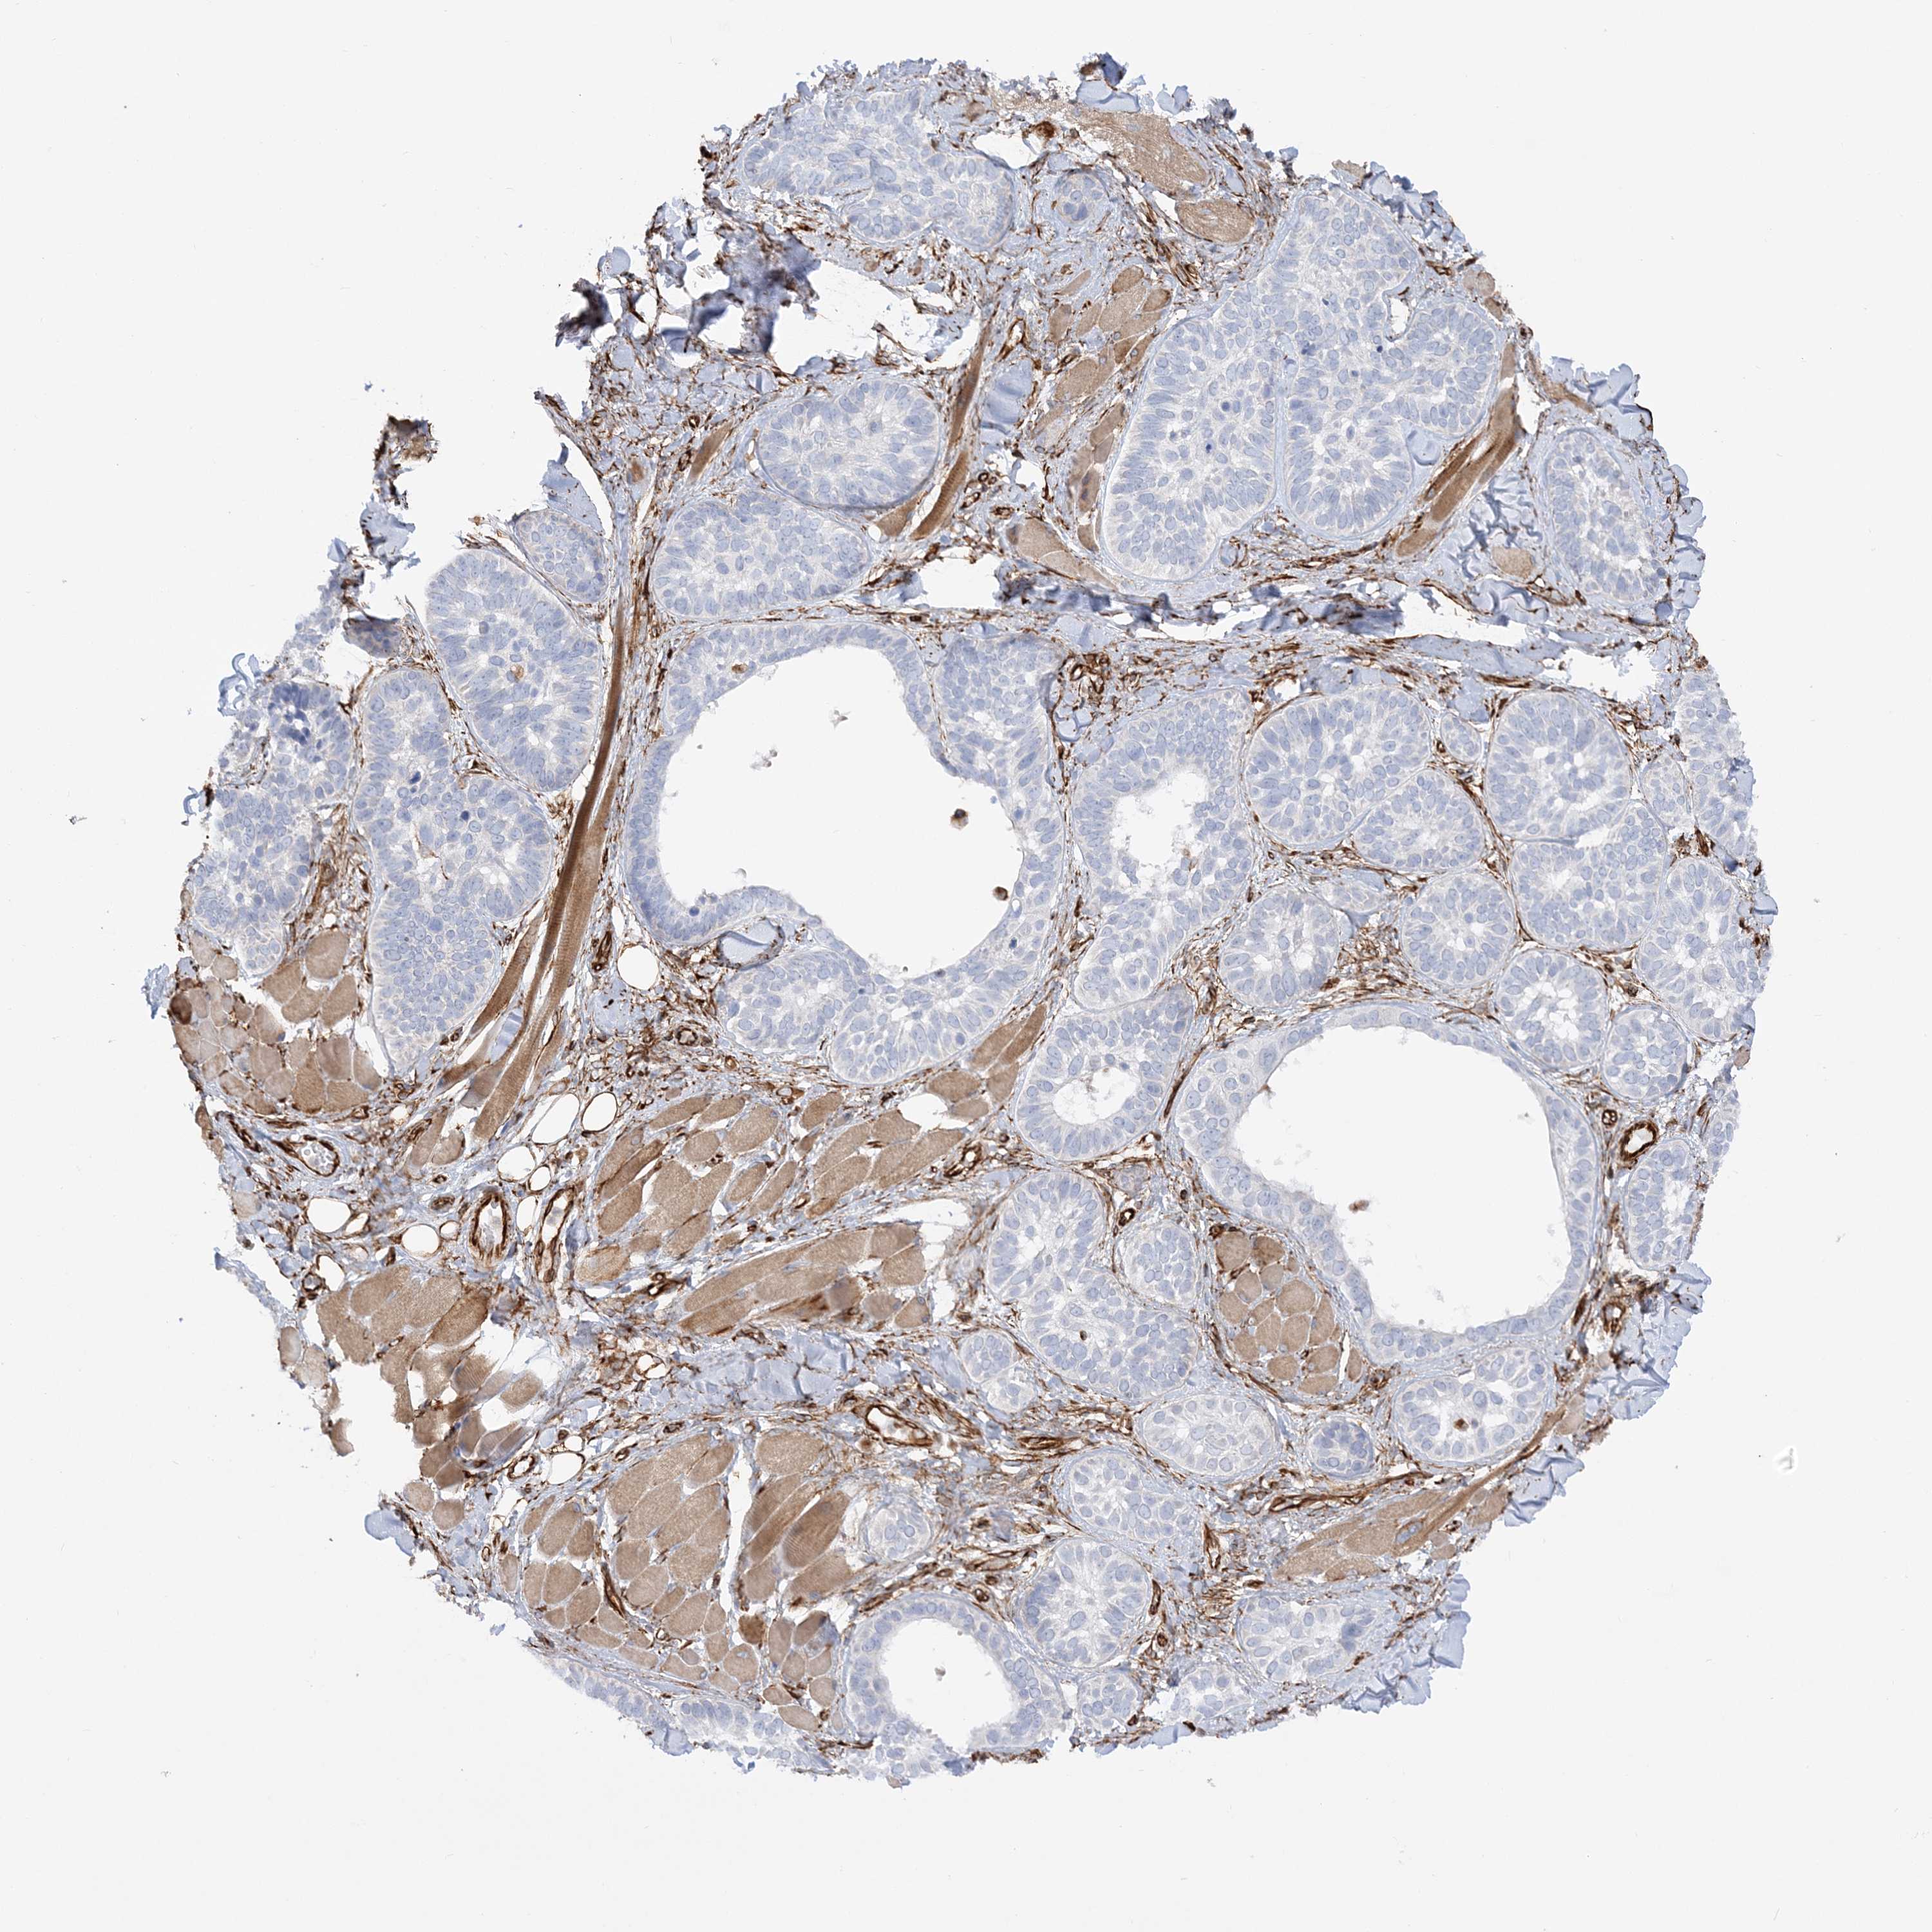

Basal cell and squamous cell cancer

SKIN CANCER - Protein expressioni

A mouse-over function shows sample information and annotation data. Click on an image to view it in a full screen mode. Samples can be filtered based on level of antibody staining by selecting one or several of the following categories: high, medium, low and not detected. The assay and annotation is described here.

Antibody stainingi

Antibody staining in the annotated cell types in the current human tissue is reported as not detected, low, medium, or high, based on conventional immunohistochemistry profiling in selected tissues. This score is based on the combination of the staining intensity and fraction of stained cells.

Each image is clickable and will lead to virtual microscopy that enables deeper exploration of all samples and also displays staining intensity scores, fraction scores and subcellular localization as well as patient and tissue information for each sample.

Antibody HPA036560

Antibody HPA036561

Staining

High

Medium

Low

Not detected

Intensity

Strong

Moderate

Weak

Negative

Quantity

>75%

75%-25%

<25%

None

Location

Nuclear

Cytoplasmic/membranous

Cytoplasmic/membranous,nuclear

Basal cell carcinoma